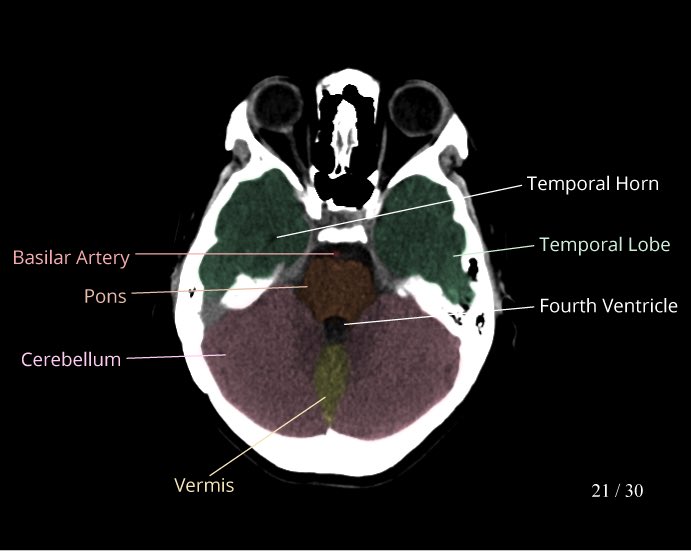

نبدأ بأشعة مقطعية طبيعية للرأس

Normal head CT scan

Non contrast

صور جدا مفيدة للاناتومي: 👇🏻

ويقصد فيه Cisterns

عبارة عن مساحات مليانة "CSF” ومتصلة ببعض عشان ال CSF circulation تمشي بسلاسة

Related pathology

Mass effect and ICP effacing 1 or more of the cisterns

Subarachnoid hemorrhage

arachnoid cyst